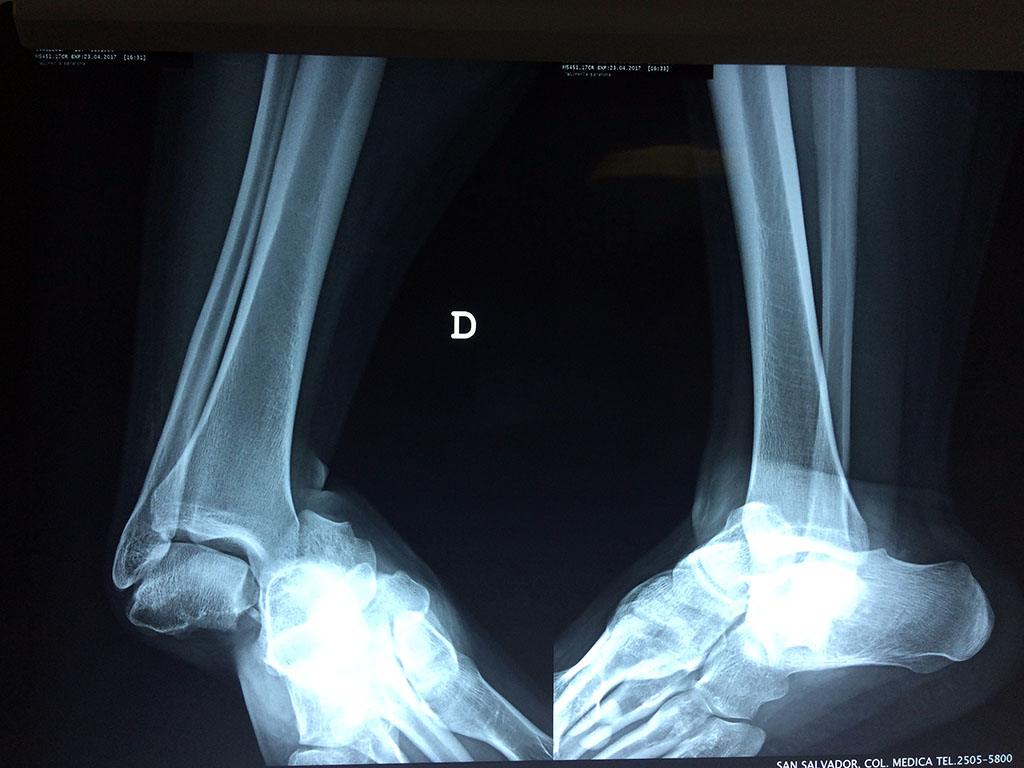

Una fractura de tobillo es la rotura de uno o más de los huesos del tobillo. Estas fracturas pueden ser:

- Parciales (el hueso está sólo parcialmente fisurado, no del todo).

- Completas (el hueso está perforado y está en 2 partes).

- Producirse en uno o ambos lados del tobillo.

Algunas fracturas de tobillo pueden requerir cirugía si:

- Los extremos de los huesos están desalineados entre sí (desplazados).

- La fractura se extiende hasta la articulación del tobillo (fractura intra-articular).